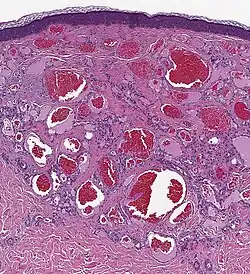

Histologie

- lobuläres Gefäßmuster des vaskulären, kanalisierten Tumors

- fokale Mikrothromben

- mittelkalibrige, arborisierende Gefäße